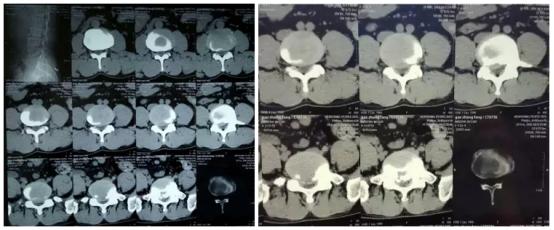

CT